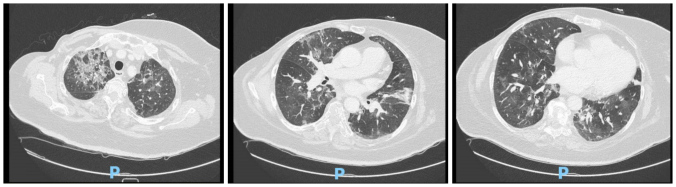

Case description: A 61-year-old woman with metastatic breast cancer treated with palbociclib and corticosteroids was admitted with fever and general weakness. Chest radiography and computed tomography showed bilateral consolidation. She was diagnosed with severe cellular immunodeficiency, very low CD4+ T cell count and several opportunistic infections including Pneumocystis jirovecii pneumonia (PCP).